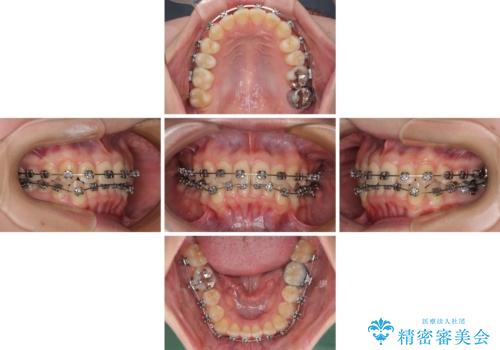

前歯のクロスバイト ギラギラのワイヤー装置で矯正治療

- 矯正装置

- メタルブラケット

- 前歯のクロスバイトを改善したいとのことで来院された患者様です。

マウスピース矯正では前歯の神経への負担が大きいことを懸念され、ワイヤー装置による矯正治療を行うこととしました。

クロスバイトが改善する際は、前歯しか接触しないため、痛みがあったり食事が取りにくかったりと、不便な時期がありますが、1年強の短期間で無事に治療を終えることができました。